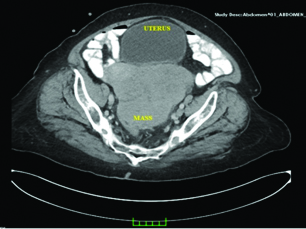

A 65-year-old, G3, P3 woman referred to gynaecology clinic due to sensation of fullness in the pelvis and a palpable mass in the abdomen since 2 weeks. She had a medical history of osteoarthritis, hypertension and non-insulin-dependent diabetes mellitus. The patient’s body mass index was 36 kg/m2. Physical examination revealed a large palpable, relatively mobile, non-tender mass in the pelvic region. Ultrasound demonstrated a loculated heterogeneous, cystic mass in pelvis and mild free fluid in the Pouch of Douglas. The lesion had mixed echogenicity with hypo echoic and hyper echoic components, contained solid parts within distinct margins, and were 18cm×15cm×12cm in size. Computed tomography was performed because the lesion extended beyond the pelvis [Table/Fig-1]. Computed tomography showed a large complex, well-circumscribed mass measuring 18 cm in the largest transverse diameter occupying the pelvis. Her CA-125 levels were 36U/L. Based on the clinical findings and imaging studies malignancy was highly probable, so the patient was prepared for surgery. The patient underwent an exploratory midline laparotomy from above the umbilicus to the symphysis pubis. At surgery, the pelvic and abdominal organs were closely inspected. The tumour originated from the left ovary and abdominal ascites was noted. The gross appearance of the tumour was predominantly solid and lobulated mass, with varying degrees of haemorrhage and necrosis. We found that no organ was infiltrated, and the right ovary was atrophied. Peritoneal washings were obtained. Frozen section revealed a malignant tumour. The patient then underwent comprehensive surgical staging procedures, including transabdominal hysterectomy and bilateral salpingo-opherectomy, infracolicomentectomy and bilateral pelvic and para-aortic lymphadenectomy. A histopathological examination demonstrated Malignant Mixed Mullerian Tumour of the Ovary (OMMMT) and the patient was diagnosed with surgical stage IA disease [Table/Fig-2,3 and 4]. Adjuvant chemotherapy consisting of systemic Paclitaxel (175 mg/m2) and Carboplatin (area under the curve = 6.0) every 3 weeks for six cycles was offered. The patient tolerated chemotherapy well without any significant adverse events. Currently, one year after completing the chemotherapy, the patient showed no evidence of recurrent disease.

Computed tomography showed a large complex, well-circumscribed mass measuring 18 cm in the largest transverse diameter occupying the pelvis.